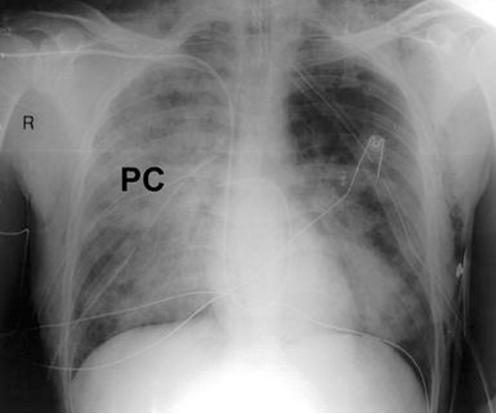

Answer: C) S1Q3T3 pattern on ECG

Explanation:

This 45-year-old man has a confirmed massive pulmonary embolism (PE) with clinical signs of right ventricular strain. The S1Q3T3 pattern on ECG is a hallmark finding associated with severe right ventricular strain caused by acute pressure overload.

• The S1Q3T3 pattern refers to the presence of a deep S wave in lead I, a Q wave in lead III, and an inverted T wave in lead III. This finding indicates right heart strain, commonly associated with massive or submassive PE.

• Right ventricular strain occurs when the right ventricle struggles to pump against the sudden increase in pulmonary artery pressure caused by the embolism.